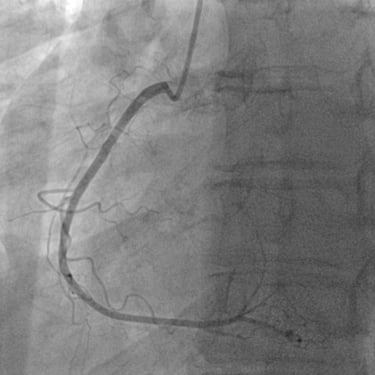

CORONAROGRAFIA

La Coronarografia è l’esame piu’ approfondito per valutare la presenza di restringimenti (“stenosi”) a carico delle arterie coronarie, ovvero delle arterie che nutrono il cuore. Viene effettuata tramite utilizzo di appositi cateteri che vengono inseriti attraverso l'arteria radiale o femorale. Per acquisire le immagini viene utilizzato un liquido chiamato “mezzo di contrasto” che opacizza il lume delle arterie mescolandosi al sangue. Le immagini vengono acquisite da un macchinario che emette una debole radiazione e registra le immagini.